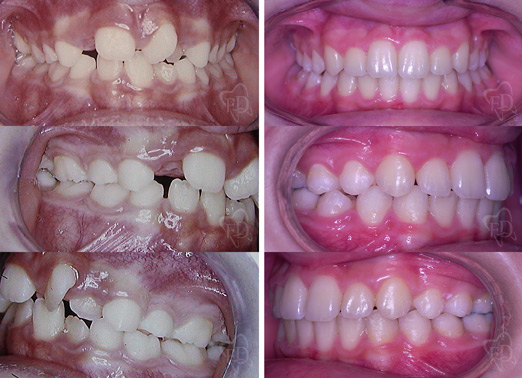

II classe con estrazioni:

prima dopo